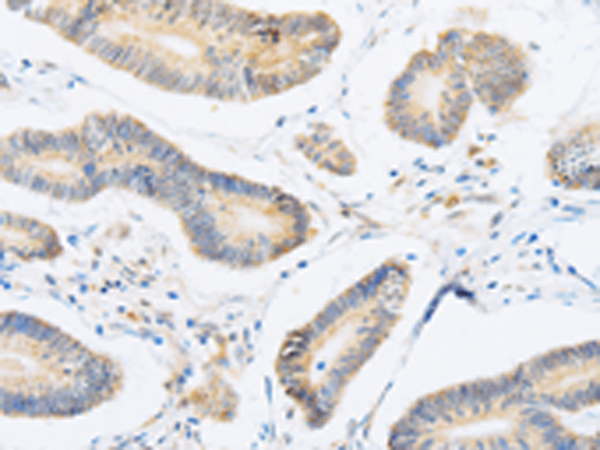

分类: 科研抗体货号: P00813别名: LABH1应用: IHC反应种属: Human